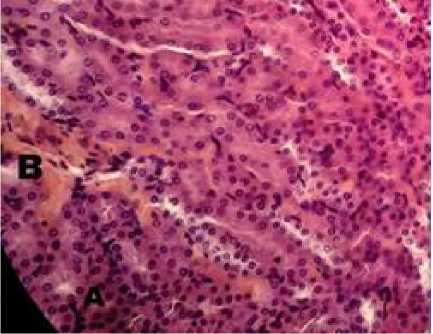

Gambar 1. Gambaran histopatologi ginjal mencit (Mus musculus) P0 (HE, 400×). Terlihat adanya perdarahan dan nekrosis. Terlihat adanya nekrosis (A) dan perdarahan (B).

Hasil pengamatan gambaran mikroskopis tubulus proksimal ginjal mencit menunjukkan adanya variasi lesi

perdarahan, degenerasi melemak, dan nekrosis. Kerusakan terjadi pada seluruh kelompok mencit baik kontrol maupun kelompok yang diberi ekstrak etanol sarang semut dosis 100 mg/kg BB, 200 mg/kg BB, dan 300 mg/kg BB. Lesi perdarahan pada pemberian ekstrak etanol sarang semut dosis 100 mg/kg BB, 200 mg/kg BB, dan 300 mg/kg BB tampak meningkat. Hal ini mungkin merupakan tanda perbaikan dari sel-sel akibat pemberian ekstrak sarang semut. Berata et al (2011) melaporkan bahwa pada jaringan yang mengalami perbaikan umumnya terjadi peningkatan vaskularisasi, sehingga tampak seperti perdarahan.